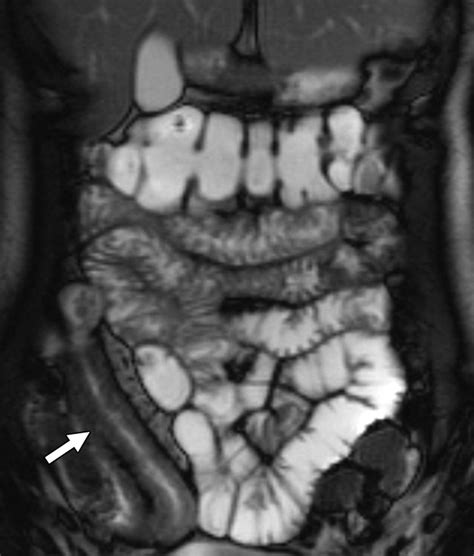

• MRI Enterography: Similar to CT enterography but uses magnetic resonance imaging instead of X-rays, making it a radiation-free option.

• Mucosal Pattern: The appearance of the lining of the small intestine, which can indicate inflammation or other abnormalities.

• Structural Abnormalities: Any visible abnormalities such as strictures, fistulas, or masses that may indicate disease.